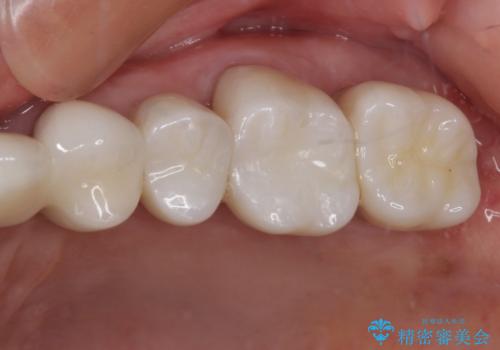

[MTMを行い歯の神経を保存] 歯周補綴ブリッジ

![[MTMを行い歯の神経を保存] 歯周補綴ブリッジの症例 治療後](https://seimitsushinbi.jp/wp/wp-content/uploads/2021/04/75330aaa19199048b71f28658fe46b5b-1-500x350.jpg?v=1618452202)